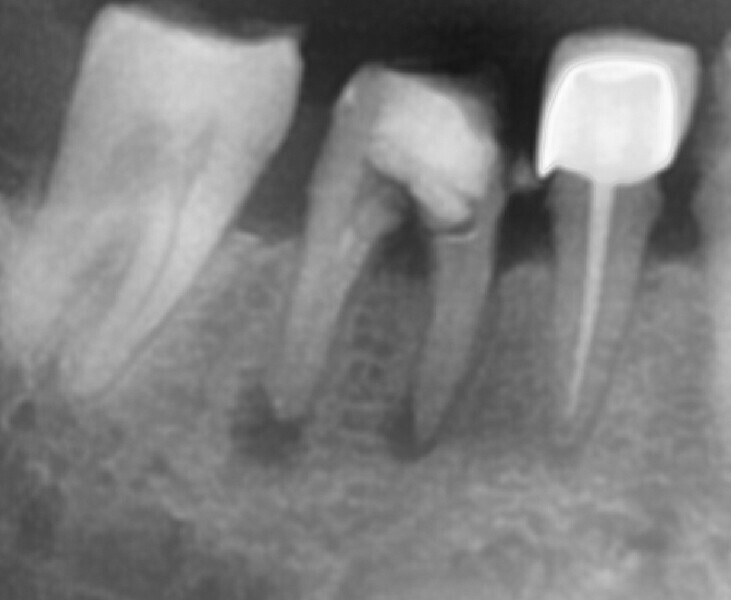

Fig.1a: Pre-op radiograph taken by the referring dentist.

Fig.1b: Pre-op radiograph taken by the author in relation to tooth #46 (January 2019).